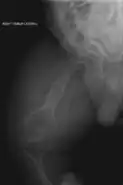

OI—especially its severe form type III—also has effects on the gastrointestinal system. It was found to be associated with recurrent abdominal pain and chronic constipation in two studies on patients affected by OI.[40][41] Chronic constipation is especially common,[1]: 377 and is thought to be aggravated by an asymmetric pelvis (acetabular protrusion).[1]: 377 [41] Especially in childhood, OI-associated constipation may cause a feeling of fullness and associated food refusal, leading to malnutrition.[1]: 377

Spinal fusion can be performed either as a preventative measure or to correct existing scoliosis, although the inherent fragility of OI bone makes this operation more complex in OI patients than it does with patients who have adolescent idiopathic scoliosis, but normal bone density.[121] Despite the risks, however, three Nemours–duPont orthopedic surgeons who specialize in surgical intervention for osteogenesis imperfecta recommend operating if the curve is greater than 50° after a child is past peak height velocity, as the spine's curve can continue to worsen even into adulthood.[13]: 104